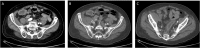

Presentation of case: The patient is an 83-year-old male who presents with severe sepsis, right lower quadrant and right leg pain. Additional past medical history is significant for rectal cancer status post resection and radiation therapy in 1997. Computed tomography (CT) on admission revealed a right iliopsoas muscle abscess, an inflamed Appendix and a pseudo aneurysm arising from the right external iliac artery. After consultations by multiple specialties, the plan was to proceed with percutaneous drainage of the abscess, antibiotic therapy and subsequent repair of the pseudoaneurysm. CT guided drainage of the iliopsoas abscess was performed with return of hemorrhagic fluid. Due to the concern of contained pseudoaneurysm rupture, the patient was taken for expedited repair. Due to the patient's frailty and hostile abdomen, we performed embolization of the right external iliac artery pseudoaneurysm with Amplatzer I plugs (St. Jude Medical, St. Paul MN) and left common femoral to right superficial femoral bypass with cryopreserved cadaveric femoral vein. Following pseudoaneurysm exclusion, continued percutaneous drainage and antibiotic therapy, the patient has done well with no further evidence of infection.

Conclusion: Repair of infected pseudo aneurysms can prove challenging. Ongoing infection, a hostile surgical abdomen and patient frailty further complicates the treatment of these patients. This case displays a minimally invasive approach to this rare but morbid condition.